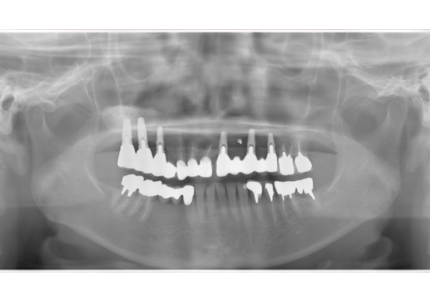

↑ 2025年9月9日

治療後は経過良好